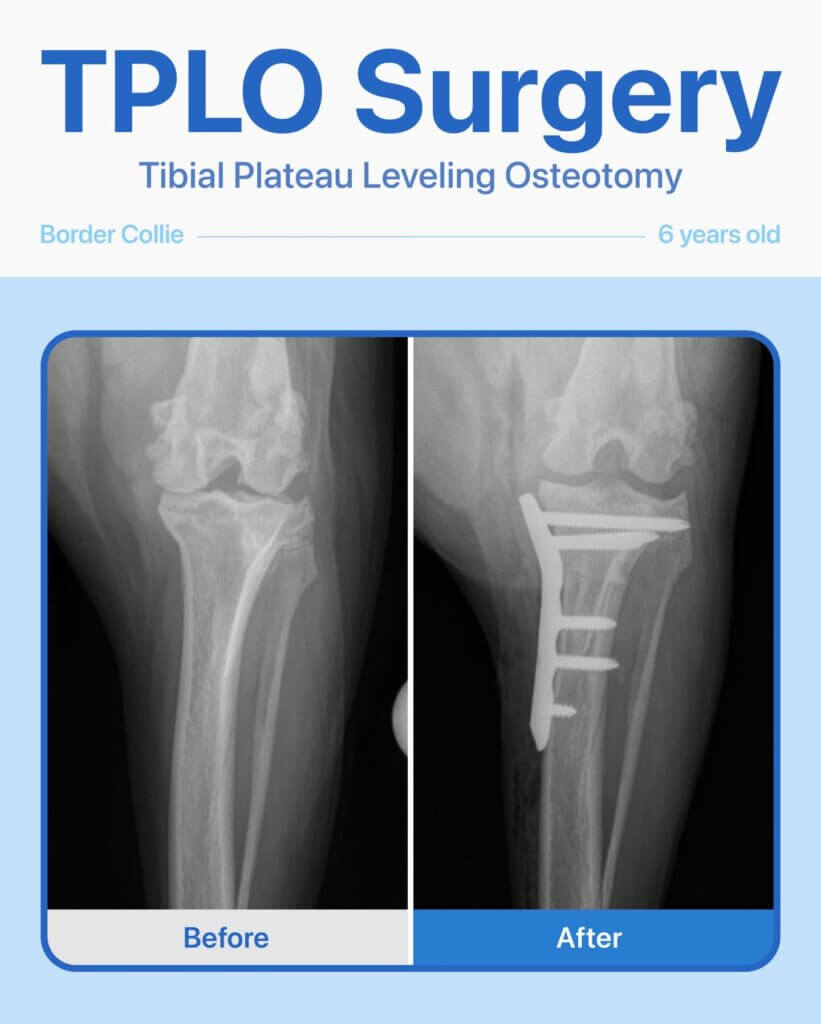

This 6-year-old female Border Collie came to us for a second opinion after showing persistent limping and reluctance to put weight on her back left leg. She had already been evaluated at another hospital, but her family wanted to explore all options.

After radiographs and a thorough orthopedic exam, our team diagnosed a torn cranial cruciate ligament (CCL). To restore stability to her knee and help her return to an active, pain-free life, TPLO surgery was recommended.